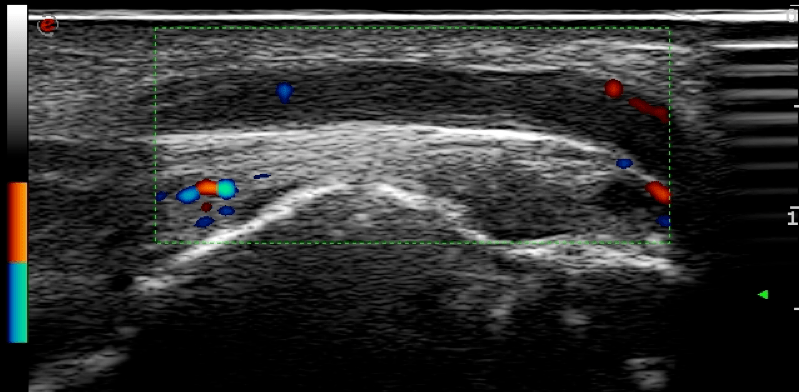

图4

尺神经主干可见异常血流信号。